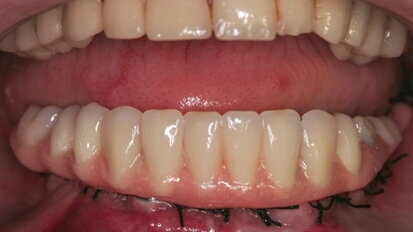

Restoring implants using lithium-disilicate,CAD/CAM fabricated restorations

Today’s consumers are always searching for the ultimate bargain, even when it comes to their dental care. They want high-quality results and minimally...